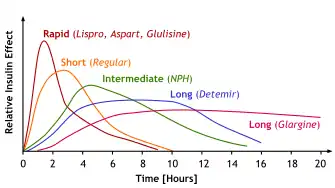

While all types are commonly referred to as insulin, the term in its strictest sense applies to the naturally occurring molecule, whereas insulin analogues have modified structures to alter their pharmacokinetics.[8]

Rapid-acting

Insulin glulisine

Insulin glulisine is a rapid-acting modified form of insulin used to treat diabetes. It differs from human insulin by replacing the amino acid asparagine at position B3 with lysine and the lysine at position B29 with glutamic acid.[56] When injected subcutaneously, it enters the bloodstream faster than regular human insulin (RHI).[57] It was developed by Sanofi. The most common side effect is hypoglycemia (low blood glucose levels).[58]

Short-acting

Regular insulin

Intermediate-acting

NPH insulin

Long-acting

Insulin detemir

Ultralong-acting

Insulin degludec